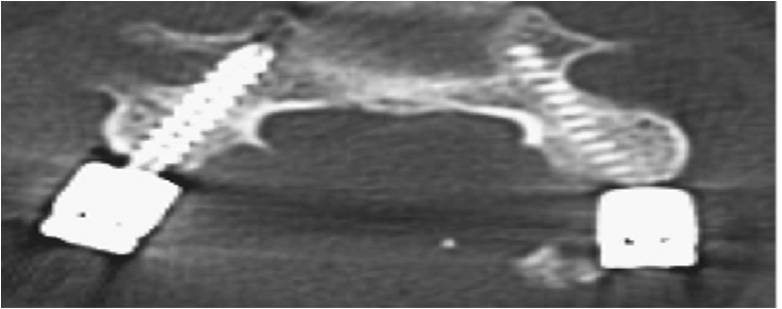

- α

- β

Εικόνα 7 (α,β): Διαυχενικές βίδες που έχουν τοποθετηθεί με καθοδήγηση από το σύστημα πλοήγησης O-arm σε αυχενικό σπόνδυλο. Εδώ απαιτείται μέγιστη ακρίβεια για την όδευση της διαυχενικής βίδας καθώς η διάμετρος του μίσχου είναι πολύ μικρή περίπου 4mm.